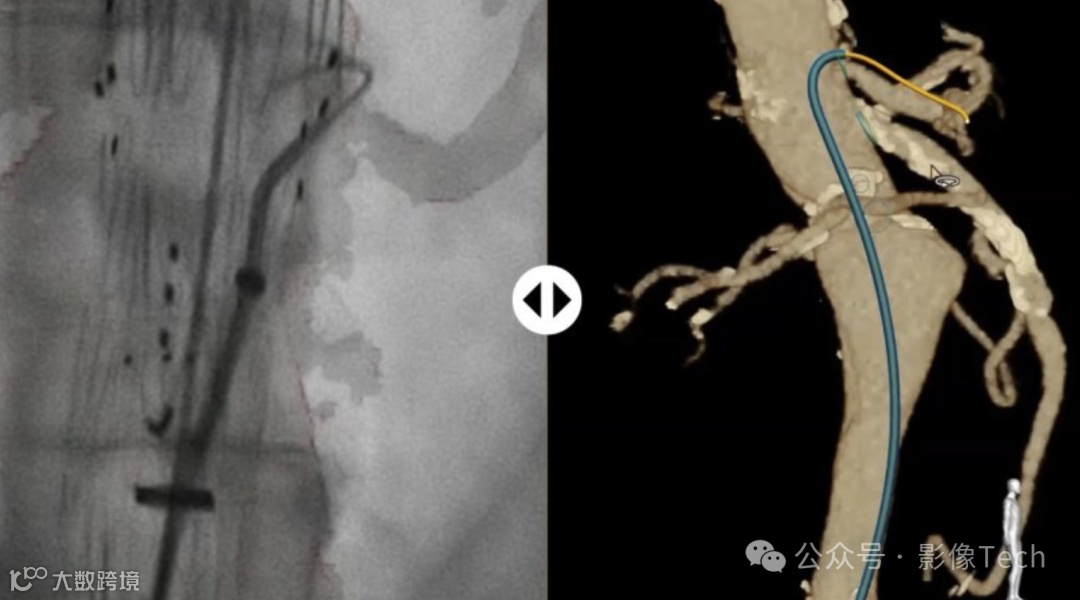

这项名为LumiGuide的技术,由Fiber Optic RealShape (FORS) 技术驱动,使得医生可以使用光来导航血管,而非X射线,被形象地称为“由光驱动的3D人体GPS”,实现了介入设备在体内的实时3D可视化,不同于传统的X射线,FORS技术使用光脉冲,显著减少了患者和医生的辐射暴露,有希望为影像行业带来新一轮的变革。

利用FOR技术的导丝集成了极细的光纤,通过发射光脉冲并分析反射信号,可在不同的成像系统(如CT扫描和X射线)上重建和可视化设备形状。

LumiGuide通过在导丝内的光纤中反射光来生成3D高分辨率彩色图像,实时从任何角度和多个视角显示病人体内的器械,包括现成的导管。这意味着医生知道自己的设备朝向哪个方向,并且能够看到他们需要前进的路径。所有这些导航都无需X射线。